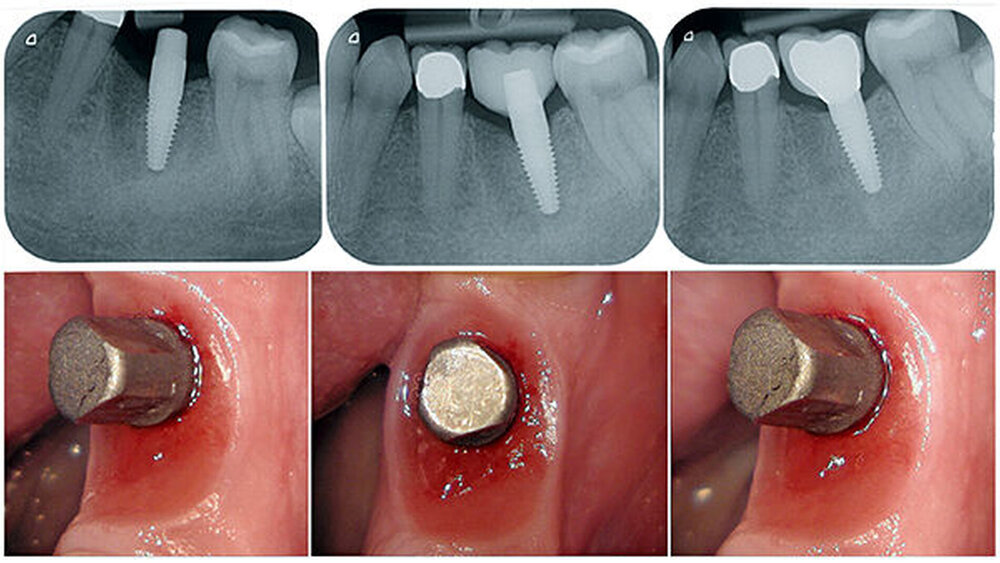

Infektionen der den Zahn umgebenden Gewebe führen infolge einer überschießenden Gewebereaktion zum Knochenabbau und im schlimmsten Fall zum Zahnverlust. Aufgrund der besonderen Situation der Perio-Integration von Implantaten und der ungenügenden Möglichkeiten der Dekontamination bakteriell belasteter Oberflächen ist ein präventiv-konzeptionelles Vorgehen notwendig. Transgingivale, möglichst einteilige Implantate entsprechen der Biologie des natürlichen Zahns eher als zweiteilige Implantate (Abb. 6, 7 und 8). Wir beobachten bei Keramikimplantaten zudem eine bessere Anlagerung der Weichgewebe.

Sofortimplantationen (auch mit Titanimplantaten) mit aus der Funktion genommenen Sofortversorgungen finden eine hohe Patientenakzeptanz, sind wirtschaftlich und aufgrund ihres biologischen Ansatzes weniger komplikationsbehaftet als aufwendige Augmentationen (Abb. 1a–1h). Insofern sollte eine Implantation bereits vor der Extraktion eines nicht erhaltungswürdigen Zahns geplant werden. Sicherlich ist es nicht möglich, den Bundle Bone, der eine Funktionseinheit des Zahnhalteapparats ist, nach einer Extraktion zu erhalten. Volumen und Dimension der Alveole und der den Zahn umgebenden Weichgewebe bleiben durch das Einbringen eines Implantats zu einem Großteil erhalten.

Das biologische, einteilig-transgingivale Implantat ist den mechanischen Einflüssen in der Mundhöhle ausgesetzt und benötigt bei geringer Primärstabilität (< 50 Ncm) unter Umständen eine zusätzliche Immobilisierung durch Verblockung mit den Nachbarzähnen oder Kronen. Der Scanner ist eine Möglichkeit der intraoperativen Abdrucknahme ohne die Gefahr der Inkontamination der Gewebesituation mit Abdruck- oder Provisorienmaterialien beziehungsweise der versehentlichen Inkorporation.

Zusätzlich kann das Emergenzprofil bereits intraoperativ in der Implantationssitzung gesteuert werden. Der Scan der ausgeheilten Situation vor der prothetischen Versorgung eröffnet die Möglichkeit, durch Einmatchen des Implantats in den Datensatz die subgingivale Situation zu simulieren ohne die Darstellung einer „Präparationsgrenze“ durch das Einlegen von Fäden. Diese Manipulationen sind traumatisch und zerstören die sensible hemidesmosomale Anhaftung der Gingiva- und Bindegewebsfasern an der Implantatoberfläche. Der digitale Abdruck wird die konventionelle Abformung in der modernen Zahnarztpraxis aufgrund seiner überlegenen Performance ersetzen. Den parodontologischen und minimalinvasiven Prinzipien folgend, ist die digitale Abformung von Zähnen auch in der ästhetisch sensiblen Zone angesichts der geringeren Traumatisierung der parodontalen Gewebe, der überragenden Präzision und der daraus folgenden Randpassung der Versorgung ein logischer und richtiger Weg in die Zukunft der zahnärztlichen Praxis (Abb. 10 – 14).